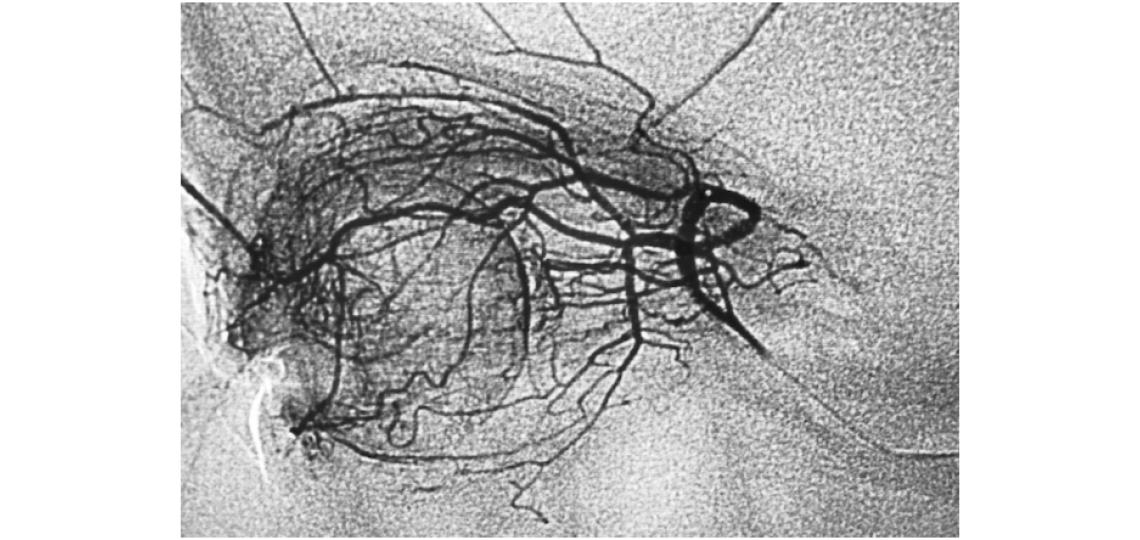

An ophthalmic angiogram obtained during selective chemotherapy infusion, demonstrates the extensive angioarchitecture that allows for concentrated regional local delivery of chemotherapy.